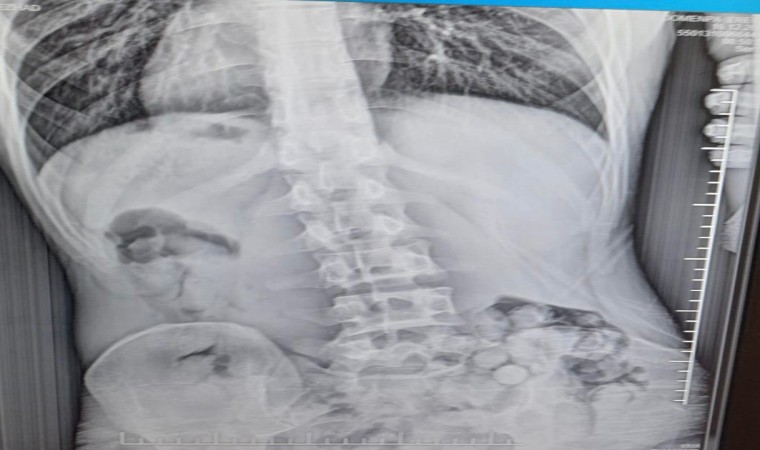

Edinilen bilgiye göre, Samsun Emniyet Müdürlüğü Narkotik Suçlarla Mücadele Şube Müdürlüğü ekiplerince Çarşamba ilçesinde düzenlenen uyuşturucu operasyonunda yabancı uyruklu R.B. (21) gözaltına alındı. R.B.’nin hastanede çekilen röntgen filminde mide ve bağırsaklarında 51 kapsül içinde toplam 309 gram metamfetamin ele geçirildi.